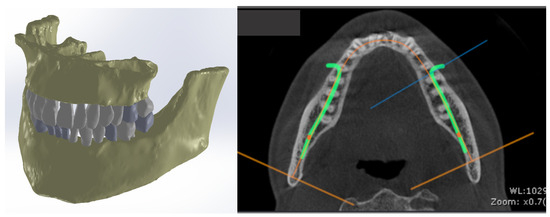

- Popa, D.; Duță, A.; Pitru, A.; Tutunea, D.; Gherghina, G. About the Simulation Environment for Dental Implant Studies. Sci. Bull. Politeh. Univ. Timis. Hidroteh. Ser. 2014, 58, 137–141. [Google Scholar]

- Vătu, M.; Crăițoiu, M.M.; Vintilă, D.; Mercuț, V.; Popescu, M.S.; Scierciu, M.; Popa, D.L. Determination of resistance forces from mandibular movements through dynamic simulation using kinematic analysis and finite elements method. Rom. J. Oral Rehabil. 2018, 10, 20–28. [Google Scholar]

- Vătu, M.; Vintilă, D.; Popa, D.L. 3D Skull Virtual Model Based on CT or MRI Images Used for Dentistry Simulations. Appl. Mech. Mater. 2018, 880, 101–110. [Google Scholar] [CrossRef]

- Petrescu, S.M.S.; Tuculină, M.J.; Popa, D.L.; Duță, A.; Sălan, A.I.; Voinea Georgescu, R.; Diaconu, O.A.; Turcu, A.A.; Mocanu, H.; Nicola, A.G.; et al. Modelling and Simulating an Orthodontic System Using Virtual Methods. Diagnostics 2022, 12, 1296. [Google Scholar] [CrossRef] [PubMed]